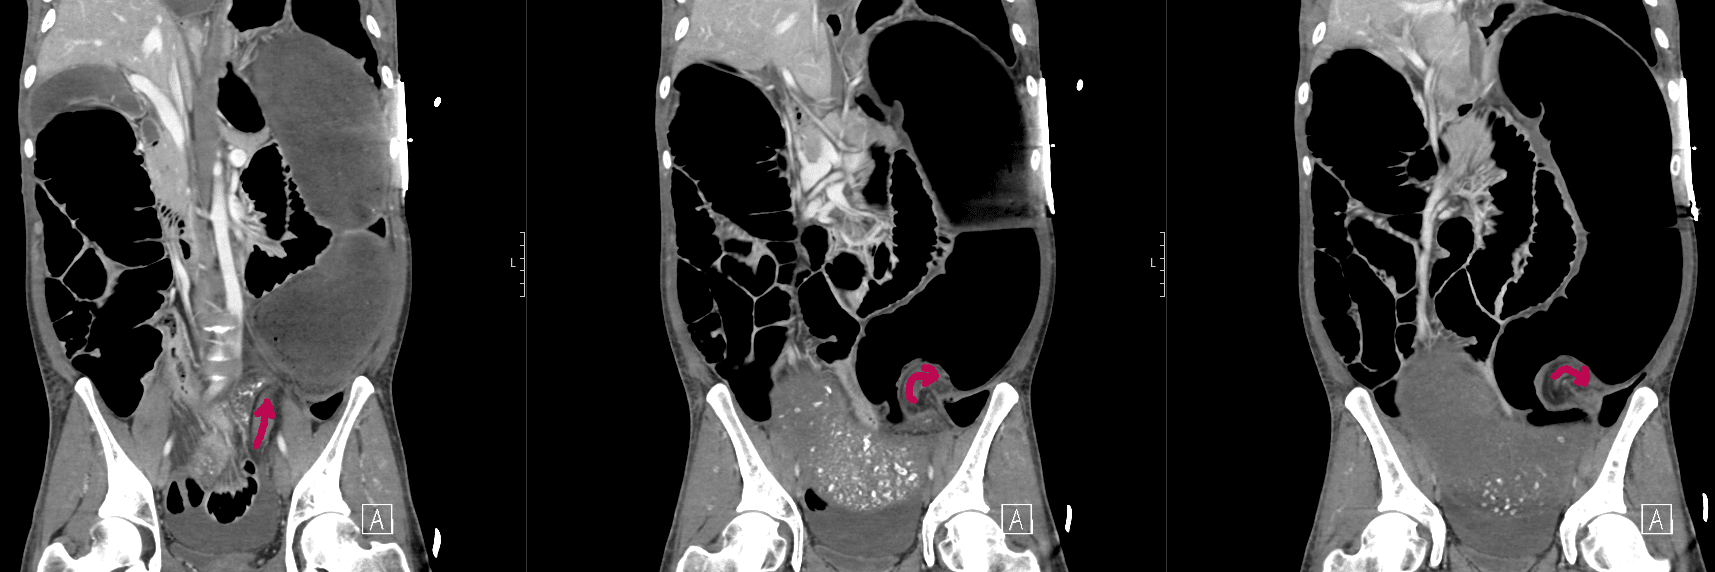

CT mesenteric angiogram

There is evidence of a sigmoid volvulus.

The proximal large bowel as well as small bowel loops are dilated suggestive of an incompetent ileocaecal valve.

There is no pneumoperitoneum to suggest hollow viscus perforation.

There is a moderate volume of free fluid. No collection.

The distended bowel compresses the liver and displaces the gallbladder and spleen posteriorly.

The abdominal aorta as well as the origins of the common iliac arteries and external iliac arteries are compressed by dilated bowel loops however remain patent and there is satisfactory flow distally to the common femoral and superficial femoral arteries.

Comment: Acute sigmoid volvulus with severe bowel obstruction. The dilated bowel loops are significantly compressing the abdominal aorta and pelvic arteries as above. Urgent surgical review recommended.